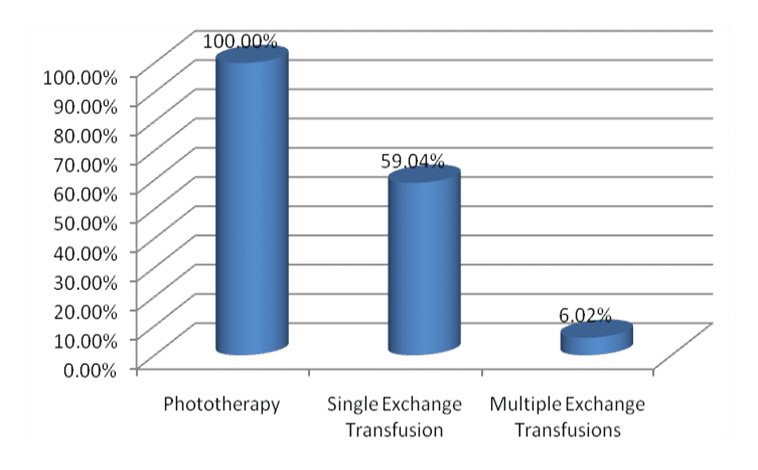

Evaluation of the Frequency of G6PD Deficiency by a G6PD Quantitative Method in Jaundiced Infants Visiting Dogar Central Kurram Hospital

Objective: To evaluate the frequency of Glucose 6 Phosphate dehydrogenase (G6PD) deficiency by a G6PD quantitative method in jaundiced infants...Read More